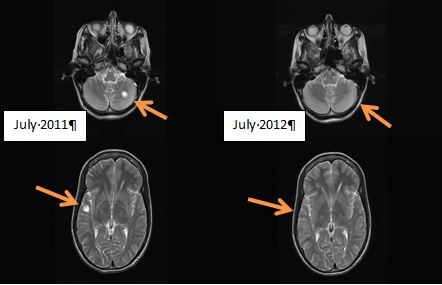

Danelle, the owner of the MRI scans above showing complete reversal MS lesions, says that her reversal was due to a vegan diet plus removal of heavy metals such as nickel, titanium due to dental procedures. See what dentist Dr Robert Gammal has to say about this:

I was diagnosed with Multiple Sclerosis in August 2011 at the age of 30. An MRI scan showed two large lesions in my brain. Prior to diagnosis, I had experienced the following symptoms over a six year period: numbness in my arms, itchiness of the upper body, fatigue, loss of taste, blurred vision and very scary double vision. After diagnosis I had some medical treatment with steroids and interferon but decided to stop this treatment due to the numerous side-effects.

One year later, the symptoms and brain lesions had gone, see image of brain scans above. Anyone can contact me via email